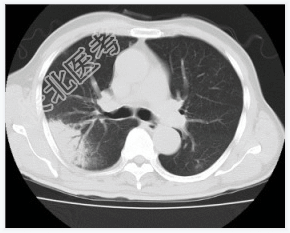

- [材料题] 患者,男性,47岁。发热,咳嗽,右胸痛3天入院。查体.体温,38℃。右上肺呼吸音减低,叩诊实音。心脏无异常。行胸部CT平扫。

- 简答题1、请问该病例诊断是什么?

- 简答题2、请问诊断依据是什么?

- 简答题3、鉴别诊断有哪些?